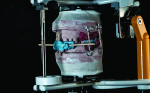

With clinician and patient approval, the case was ready for final processing. When fabricating immediate dentures, the author highly recommends using high-impact acrylic for the anterior portion in order to preserve the integrity of the prosthesis. In this case, GC Nature-Cryl Super Hi Impact acrylic (GC America, gcamerica.com) was chosen. This acrylic is available in 7 shades and is very impact resistant. To create the most esthetic denture possible, 2 shades of acrylic as well as a GC Gradia® gum (GC America) facing was used.6 The case was separated from the mounts and flasked in the traditional manner. The only modification was the use of laboratory putty on the facials of the teeth in order to allow for custom shading and the ease of deflasking (Figure 10). (Note: If only stone is used, the free monomer will etch through the separator and make removal of the stone challenging.) For this case, Nature-Cryl Light shade, which was defibered, was used in the areas of the free gingiva and the eminences.7 Light Reddish Pink was used as the base color. The case was trial packed 3 times on each arch with the use of the traditional press-packing technique and allowed to bench cure for 20 to 30 minutes. The dentures were cured for 9 hours at 165° F with a 30-minute boil afterward. When the curing was completed, the flasks were allowed to bench cool to room temperature and deflasked in a regular manner.